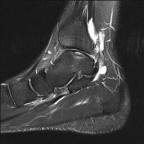

Ankle arthroscopy can be helpful for patients who have damage to the cartilage of the ankle joint. Typically sustained after an ankle sprain, some people who have continued pain may have a small piece of bone and cartilage that is loose inside the ankle joint.

Ankle arthroscopy can be used to remove the loose fragment, and perform surgery to help stimulate the growth of fibrocartilage in the defect. This is done through two small incisions at the front of the ankle. The surgery is very safe, with a very low risk of infection. The main risk is to small sensory nerves around the ankle.

Some patients also have pain at the front of the ankle when they walk, caused by spurring at the front of the ankle joint. Ankle arthroscopy can be useful to remove this spur, and improve patient’s pain when walking.